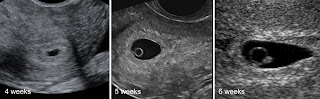

First Signs of pregnancy on Ultrasound

Everyone knows the first signs of pregnancy nausea & sickness, tender breast, missed period but what are the first signs of pregnancy

on ultrasound?

LMP = 4 weeks:-

The lining of the womb will become thickened and slightly brighter than in the "none pregnant" uterus

We may see a small cyst on 1 of your ovaries - this is nothing to worry about and is called the corpus luteum [it is what is left

behind after ovulation - and releases hormones to stop you from having a period :-) ]

LMP = 5 weeks :-

A small "black hole" (the gestation sac) will appear within the lining of the womb.

During this week a small circle will appear within the gestation sac - this is the yolk sac (just like the yolk in a chickens egg) and this will provide nourishment for the developing embryo...

Next development we see is a small line / "blob" THIS IS THE EMBRYO!

At just over 6 weeks gestational age the embryo should development heart beat (by the time the embryo measures 6mm it should be beating!)

Although sometimes we can scan sometimes see things doing a transabdominal scan (tummy scan with full bladder) the best why to scan this early in pregnancy is to do a transva**nal scan (internal scan). This does not compromise your pregnancy in any way, but allows us to use a higher frequency ultrasound probe (thus we can see smaller things more clearly).

(NB; LMP = 1st day of your last menstraul period)